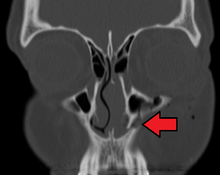

The maxillary sinus appears as a shallow groove on the nasal surface of the bone about the fourth month of development, but does not reach its full size until after the second dentition.

The maxillary sinus presents the appearance of a furrow on the lateral wall of the nose. In the adult the vertical diameter is the greatest, owing to the development of the alveolar process and the increase in size of the sinus.

Maxilla fractures is a form of facial fracture caused by a fracture. A maxilla fracture is often the result of facial trauma such as violence, falls or automobile accidents. Maxilla fractures are classified according to the Le Fort classification.